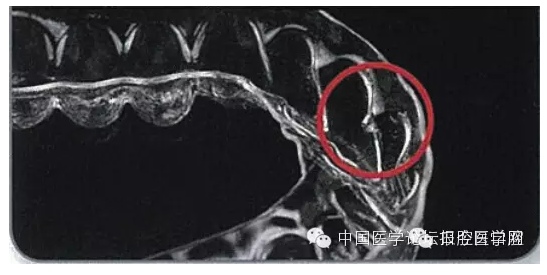

現(xiàn)代無托槽隱形矯治技術(shù)1997年最早在美國出現(xiàn),即所謂的隱適美(Invisalign)無托槽隱形矯治系統(tǒng)。2003年,國產(chǎn)EAB型無托槽隱形矯治系統(tǒng)也相繼研發(fā)成功(圖2)。之所以稱為“現(xiàn)代無托槽隱形矯治技術(shù)”,是因為該技術(shù)的產(chǎn)生與發(fā)展融合了現(xiàn)代正畸學、數(shù)字化圖像采集與處理技術(shù)、快速成型技術(shù)等多學科、多領(lǐng)域的科技成果。從三維牙頜數(shù)字模型信息采集、矯治器數(shù)字化設計、數(shù)字化可視化的醫(yī)技醫(yī)患溝通方式,到矯治器的數(shù)字化加工,計算機相關(guān)的最新成果無處不在。因而我們將該類技術(shù)稱為現(xiàn)代無托槽隱形矯治技術(shù)。該類技術(shù)首次實現(xiàn)了無托槽矯治器的個性化批量定制加工。

圖2 Simpli5矯治器和EAB型無托槽矯治器